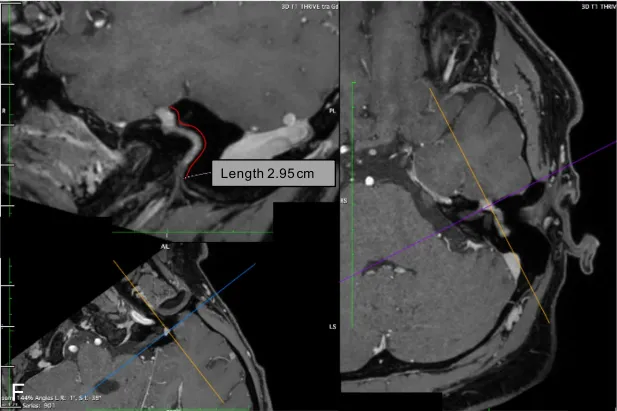

鉴于此类肿瘤可起源于神经的任何部位,必须联合进行计算机断层扫描(CT)与对比增强磁共振成像(MRI)检查。现代薄层CT能清晰显示颞骨的精细解剖结构。面神经鞘瘤通常不引起骨质"侵蚀",而是表现为特征性的扇贝样压迹及骨改建,符合良性缓慢生长肿瘤的特点。注射钆对比剂后肿瘤呈现显着强化,T2加权像呈高信号,T1加权像呈等或低信号(图1)。三维稳态构成干扰序列或三维快速成像序列可提供重要诊断信息。

对于位于桥小脑角及内耳道的肿瘤,其与前庭神经鞘瘤的鉴别诊断存在困难甚至难以区分。若肿瘤延伸至面神经迷路段,则支持面神经鞘瘤的诊断。位于脑池段及内耳道的大型面神经鞘瘤可呈现与前庭神经鞘瘤相似的"哑铃形"形态,此征象源于肿瘤穿过内耳道,扩大面神经管并进入膝状神经节窝。增强T1序列可清晰显示肿瘤强化,结合CT显示的骨质改变,可使面神经鞘瘤成为符合上述影像特征的首要鉴别诊断。